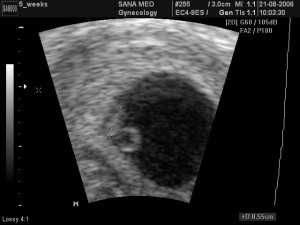

УЗИ на 2 неделе беременности

УЗИ на 2-ой неделе, фото плода

На 2-й неделе от задержки УЗИ назначают для подтверждения диагноза, а также тогда, когда есть риск, что что-то пойдет не так. На фотографиях вы можете посмотреть, как выглядит ваш будущий малыш в этом периоде развития.

УЗИ, беременность 2-3 недели

УЗИ, 2-3 недели

Вторая неделя беременности представляет собой наиболее ранний срок проведения подобной диагностики. Тем не менее, подтвердить факт беременности на этом этапе способно только сверхчувствительное оборудование. Исследование проводится трансвагинально.

Для проведения обследования женщина должна получить направление у гинеколога. Методика подразумевает введение во влагалище женщины тонкого датчика в презервативе.

Вопрос, вредно ли УЗИ на ранних сроках беременности волнует всех мам. С уверенностью можно заявить о том, что обследование никак ни влияет на развитие плода и протекание беременности, тем не менее, сонологи рекомендуют проходить УЗИ не раньше 6-8 недели. На 2 неделе беременности специалист сможет только подтвердить факт зарождения новой жизни, оценить какие-либо показатели невозможно.